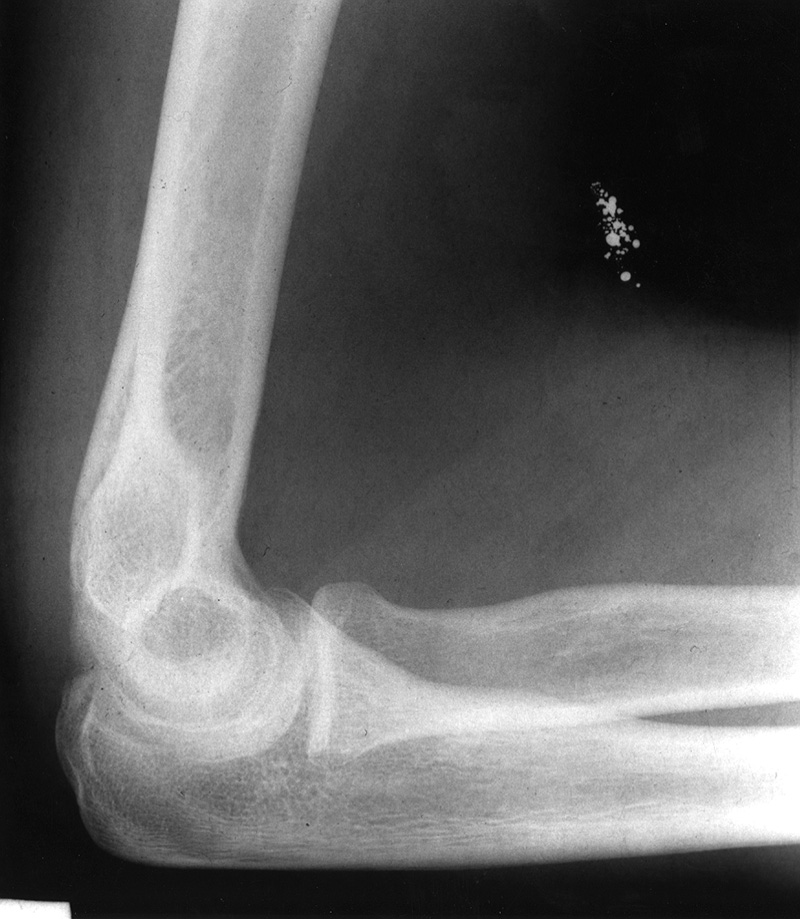

Deliberate injection of mercury subcutaneously or intravenously produces a dramatic radiographic appearance (figure: mercury in left elbow; figure: mercury in the lungs). Individuals may inject themselves in the mistaken belief that mercury increases their strength, or they may be drug abusers or even attempting suicide (Naidich, 1973; Wenzel, 1980; Peterson, 1980; Spizarny, 1987).

If mercury is injected into subcutaneous tissues, it forms irregular globules and may remain in place for months to years. If it is injected into the venous system, it will embolize to the lungs where it forms small globules in the peripheral branches of the pulmonary arteries. The mercury may also pool in the right ventricle. Differentiating aspirated metallic mercury from mercury embolism to the lungs is difficult on the basis of chest radiographic appearances alone. The diagnosis depends on the patient history, presence of mercury in the right ventricle or subcutaneous tissue of the arm or leg (favoring mercury embolism) or the presence of mercury in the gastrointestinal tract (favoring mercury aspiration) (Wenzel, 1980; Peterson, 1980; Spizarny, 1987). Surprisingly, metallic mercury in the bronchial tree or in the pulmonary arterial tree is usually not associated with symptoms, and it may remain undiscovered indefinitely.

21 year-old man who injected himself with metallic mercury.

21 year-old man who injected himself with metallic mercury. There are mercury emboli to the lungs and metallic mercury is evident in the antecubital fossa of the left elbow. (Figures courtesy of Charles A. Rohrmann, Jr, MD. They were originally printed in Peterson, 1980). Trick or treat candy. There are no hidden needles or razor blades. The candy and the apple (round density) where eaten with much enjoyment. From Hunter, 1994